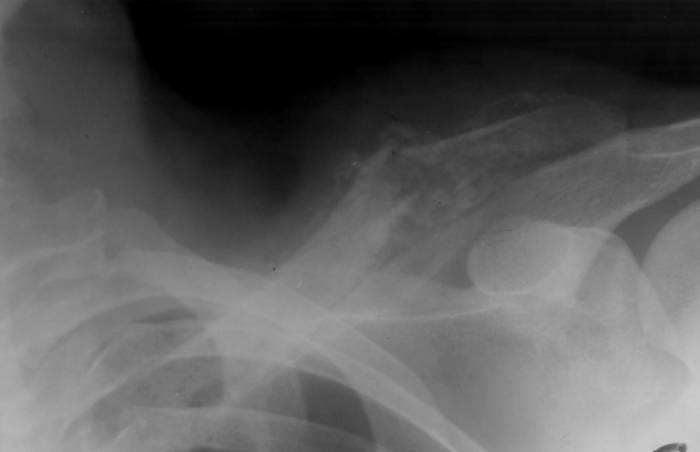

Вывихи и смещения

Вывих плечевого конца ключицы сопровождается острой болью

Грудинный конец ключицы, которым она крепится к клетке, может произойти из-за травм и падений, а также после ударов. Встречается патология редко и сопровождается такими симптомами:

- сильным отеком;

- выпячиванием ключицы или западанием;

- болью и покраснением.

Другой конец, акромиальный, имеет несколько связок, которыми крепится к лопаткам. Если они рвутся, пациент испытывает острую боль, возможность повернуть плечом резко ограничивается.

Повреждения акромиально-ключичного сустава

Этот структурный элемент находится в области лопатки и ключицы, где они пересекаются. Появляется травма преимущественно после удара или падения. Вызывает сильную боль, отечность, повышенную чувствительность области, выступы и смещения кости. Избавиться от травмы можно оперативным путем или с помощью плечевой скобы для стабилизации.